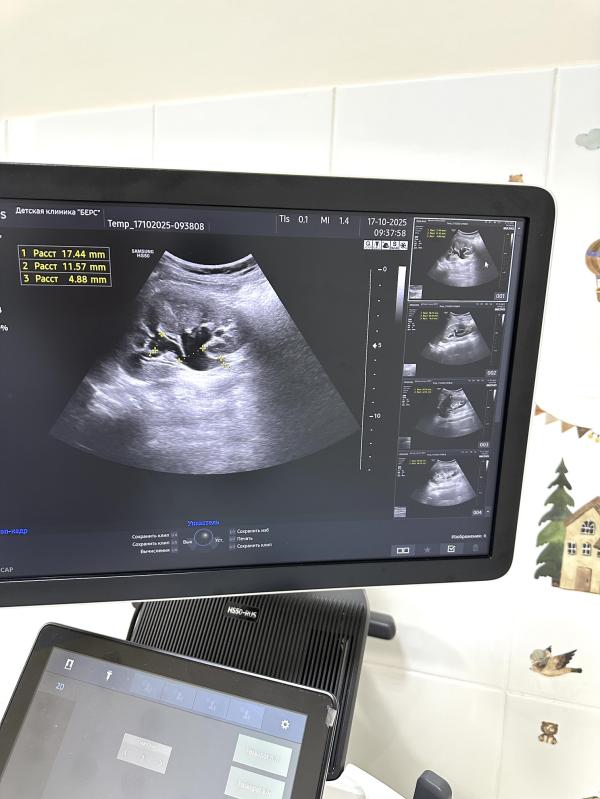

Во время осмотра врач обратил внимание на тревожащие симптомы и направил мальчика на общий анализ крови и мочи, а также УЗИ почек. Результаты обследования показали выраженное расширение лоханки, чашечек и мочеточника правой почки. Дополнительно выявили большое количество мочи в мочевом пузыре (объём мочевого пузыря составил целых! 700 мл) - хотя мальчик совсем не хотел идти в туалет.

Первый снимок демонстрирует расширенную ЧЛС поражённой почки, второй показывает сильно наполненный мочевой пузырь, а третий служит примером нормальной здоровой почки для наглядного сравнения.